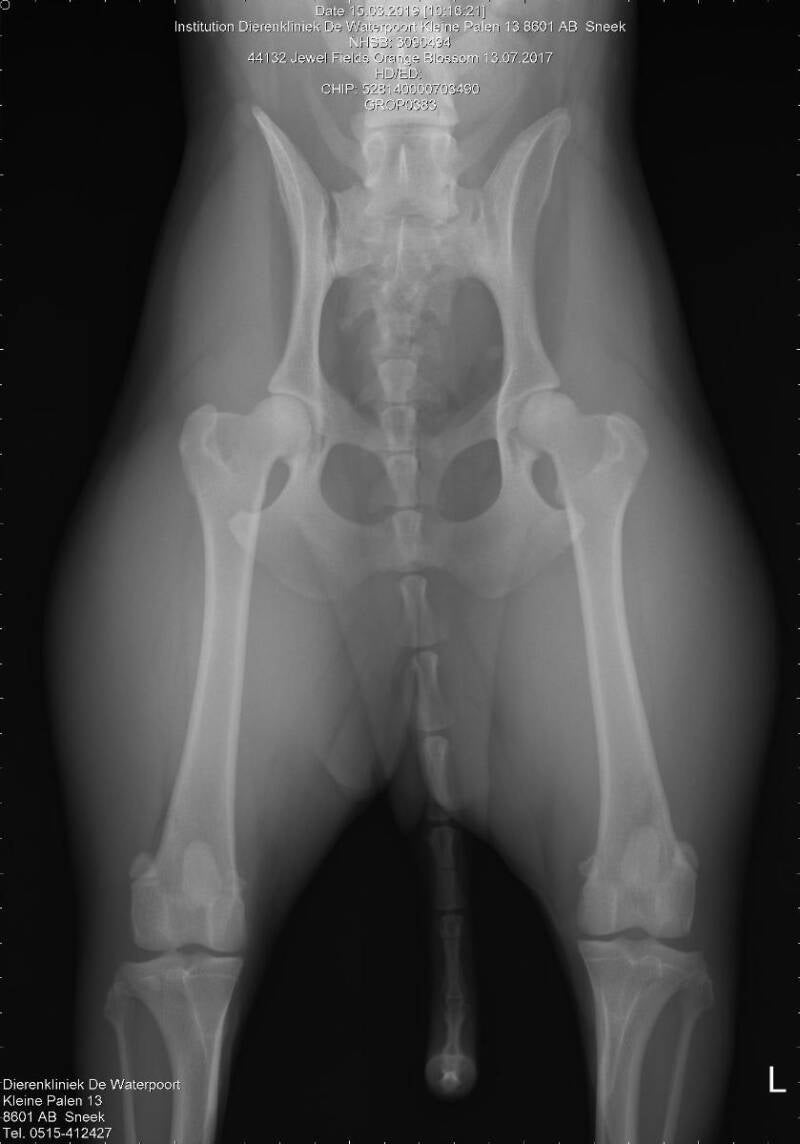

Heupdysplasie (Röntgenonderzoek)

Heupdysplasie (HD) is een misvorming van één of beide heupgewrichten. Het gevolg is dat de dijbeenkop niet meer goed in de kom van het bekken past. In Nederland mogen we dan ook alleen maar fokken met uitslagen als HD A & HD B.

Röntgen heupen

HD A1 Norbergwaarde 40 Botafwijking 0

(Jewel Fields Amareno)

HD A1 Norbergwaarde 38 Botafwijking 0

(Jewel Fields Celtic Breeze)

HD A1 Norbergwaarde 30 Botafwijking 0

(Isle of Skye Stars Border Collies)

HD A1 Norbergwaarde 37.5 Botafwijking 0

(Jewel Fields Orange Blossom)